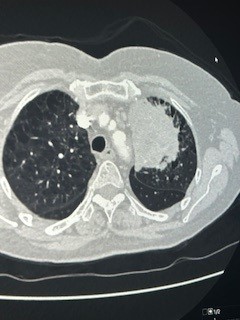

Στις φωτογραφίες 1 και 2 φαίνεται μεγάλος όγκος αριστερού πνεύμονος που εμφάνισε απόστημα και σηψαιμία. Οι λεμφαδένες που κατεγράφησαν στην αξονική και στο PetScan χαρακτηρίστηκαν καρκινικοί λεμφαδένες και το περιστατικό είχε χαρακτηριστεί ανεγχείρητο. Μια γενναία απόφαση της ομάδας μας, οδήγησε τον ασθενή σε αριστερή πνευμονεκτομή, όλοι οι λεμφαδένες ήταν αρνητικοί για κακοήθεια (ήταν έντονα φλεγμονώδεις και έδιναν ψευδή εικόνα) και κανένα από τα υπόλοιπα όργανα δεν είχαν διηθηθεί παρά τη γειτνίαση με τον όγκο (αορτή, μεσοθωράκιο, τραχεία). Η ασθενής είναι σε άριστη κατάσταση και είναι σε πρώτο κύκλο χημειοθεραπείας.

Photo 1

Photo 2